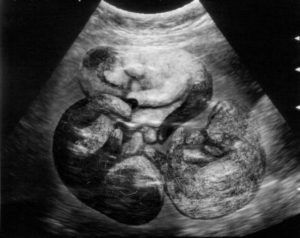

Ещё через неделю, примерно на 50-56 день беременности при осторожном прощупывании можно почувствовать головки развивающихся малышей. При желании на ощупь можно даже определить, сколько их будет. Только делать это надо очень аккуратно.

• В результате проведение процедуры УЗИ/рентгена/эхограммы после 21 дня беременности

Если вы не уверены, беременна ваша кошка или нет, то отнесите её к ветеринарному врачу, который сможет опровергнуть или подтвердить наличие беременности. Скорее всего, доктор опросит вас, чтобы собрать анамнез жизни вашей кошечки, осмотрит ее и ощупает, возможно, проведение ультразвуковой диагностики и, если срок 24-27 дней, то можно увидеть количество плодов в матке и проконтролировать их состояние.

Хорошо бы на 8-9 неделях сделать кошке УЗИ. Это позволит вам точно знать число котят и быть готовым к принятию родов.